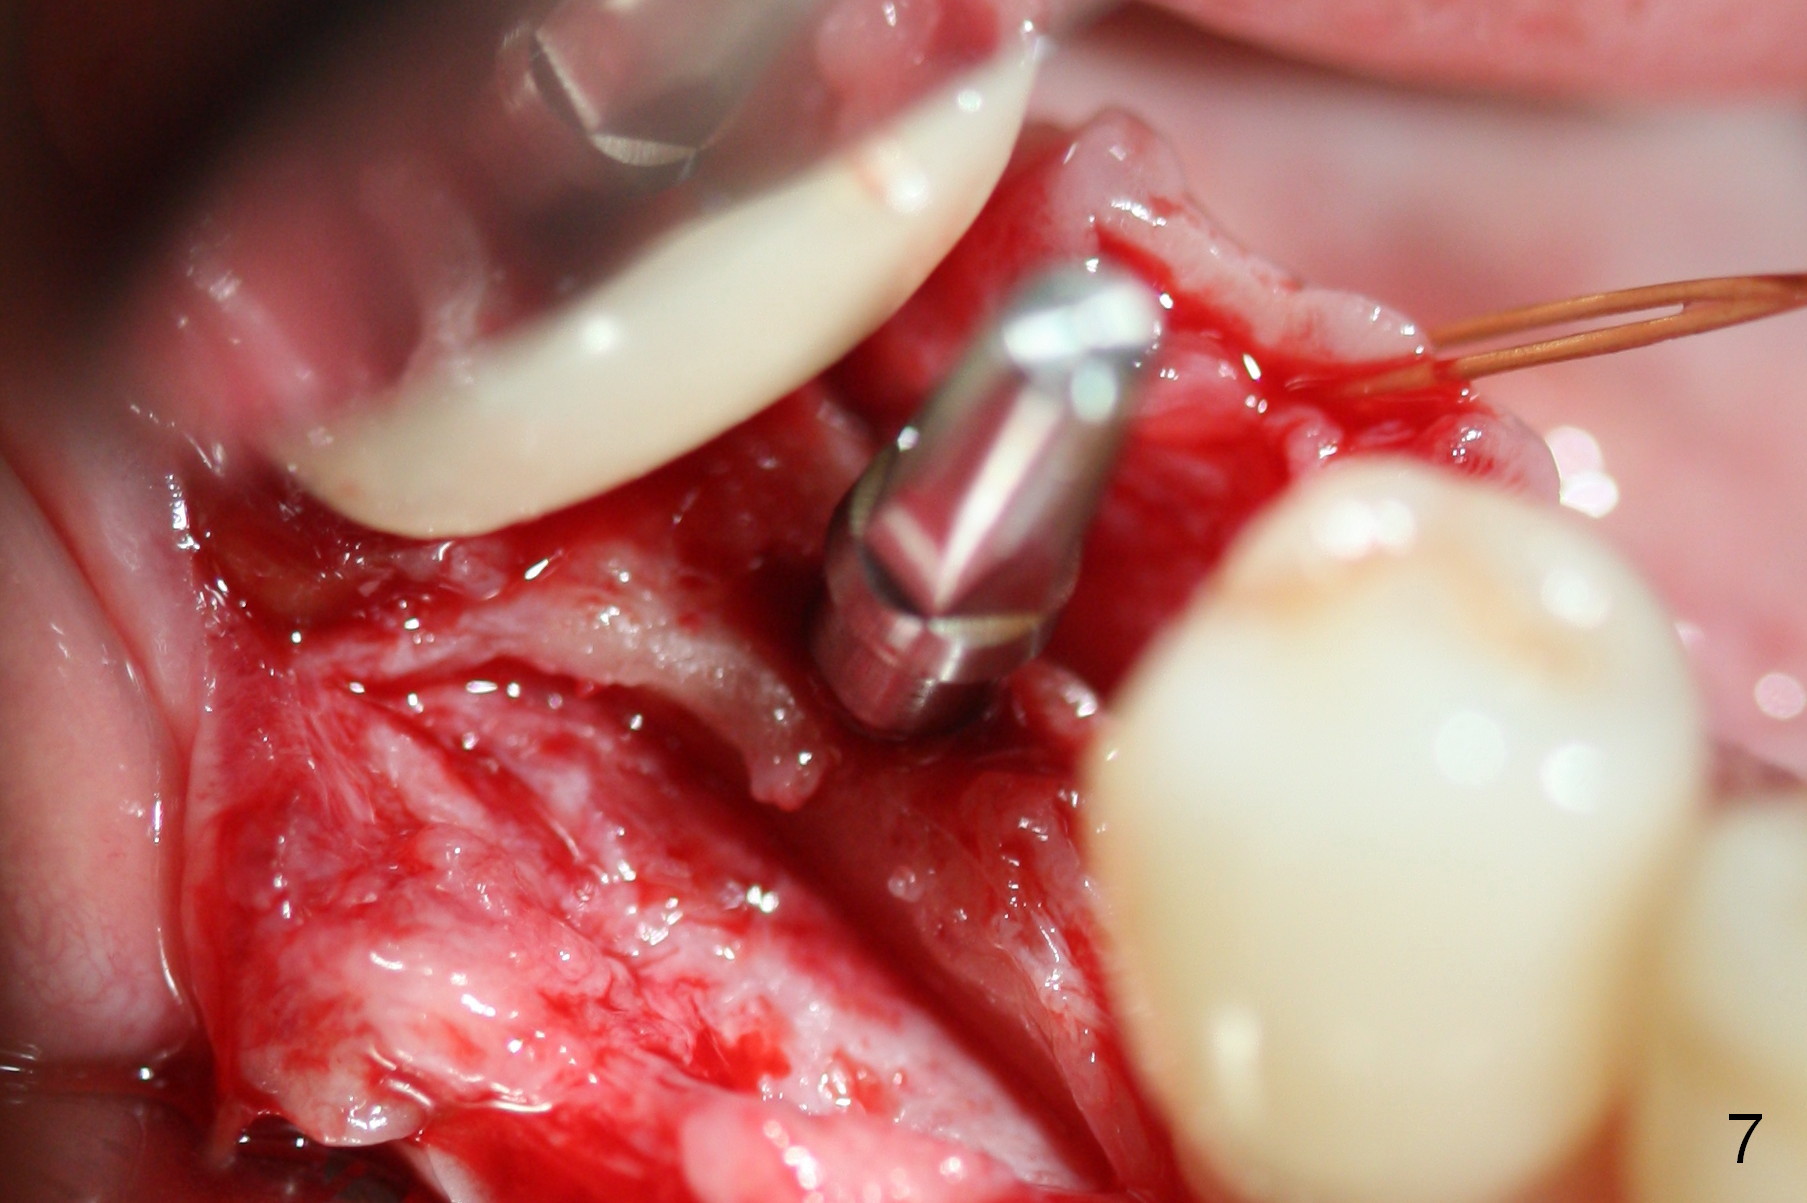

Preop photo shows the distal inclination of the tooth #28 (Fig.1). The distal surface of the latter is reduced before incision for implant placement at #29 (Fig.2). The buccolingual width is approximately 4 mm, as compared to 3 mm implant positioner (Fig.3). After 1.2x10 mm osteotomy (Fig.5), the mesiodistal cortical bone is removed with a small high-speed fissural bur (Fig.4). When a 2.5x12(2) mm 1-piece implant is placed (Fig.6), there is no buccal (Fig.7) or lingual plate perforation. There is no postop paresthesia. There is mild bone loss distal 4 months postop (Fig.8 *). Take photos before and after permanent crown cementation to show increase in ridge width after bone graft and improvement in gingival health after provisional modification. Take PA and/or BW post cementation to show that the distal bone resorption (Fig.8 *) is partially due to angulation. No continuous bone loss 15 months post cementation (Fig.9). There is mild bone resorption mesially 2 years 3 months post cementation (Fig.10). The soft and hard tissues remain healthy 4 years 3 months post cementation (Fig.11,12).